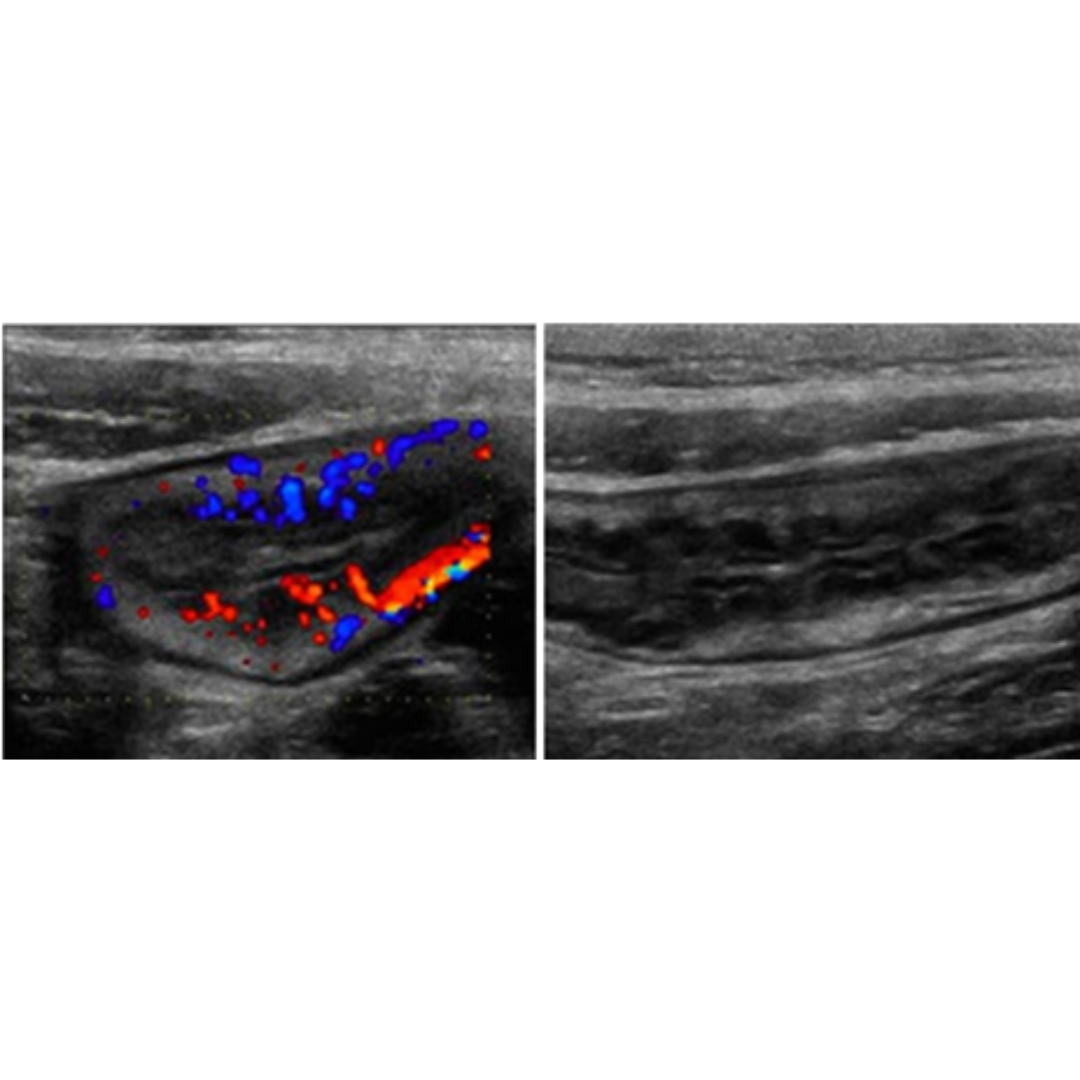

Signos US: Engrosamiento de la capa submucosa, lesiones segmentarias (tramos de intestino afectado se intercalarán con tramos sanos), hiperemia de la pared intestinal, grasa adyacente hiperecogénica, pérdida del peristaltismo, ganglios mesentéricos reactivos. En algunos casos se observa signo de “pseudoriñón” cuando la afectación es transmural.

Figura 5: Hiperemia y engrosamiento parietal irregular sin pérdida de la estratificación intestinal.

Figura 6: Engrosamiento Transmural, se observa signo de pseudoriñón, que indica pérdida de la estratificación intestinal.